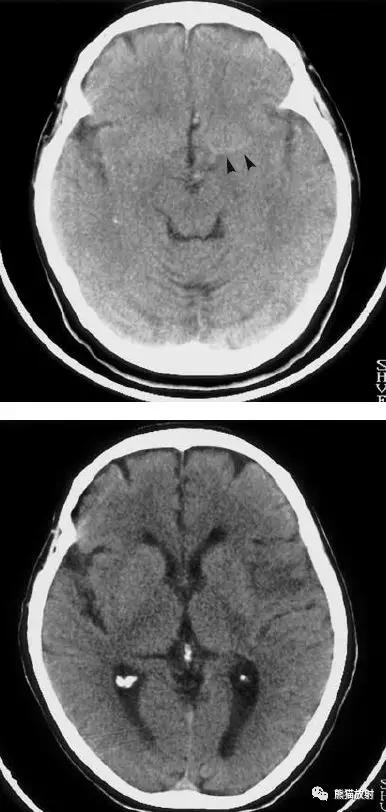

左侧大脑中动脉血栓形成(箭头)—— “大脑中动脉高密度征”,发病后不久行CT检查:相应的血管区域见缺血性病变。

右侧豆状核梗死灶(发病后15d),明显均匀强化。另左侧丘脑见腔隙性梗死灶。